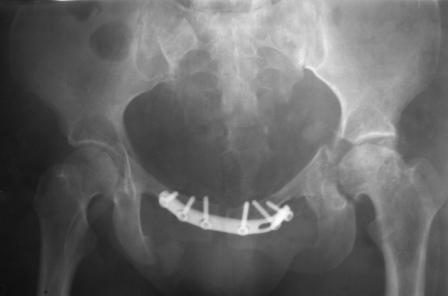

Уважаемые коллеги! Пациентка 32 года с застарелым повреждением таза, после остеосинеза лонного сочленения пластиной. Посоветуйте с выбором тактики и методик лечения.

Получила травму в феврале 2004г в г.Лобытнанги ЯНАО Тюм.обл. Через неделю после поступления выполнен остеосинтез лонного сочленения пластиной. 1,5 месяца на скелетном вытяжении. В последующем ходит при помощи костылей с нагрузкой на правую ногу. Имеется нестабильность половин таза, неправильно-консолидированный перелом левой вертлужной впадины, невропатия седалищного нерва слева. В результате невропатии седалищного нерва сформировалась эквинусная установка левой стопы, парестезии по подошвенной поверхности.

Направлена к нам для устранения патологической установки стопы и эндопротезирования левого тазобедренного сустава, также имеется миграция шурупов пластины, фиксирующей лонное сочленение.

Клинически: ходит на костылях с нагрузкой на правую ногу. Левая стопа в эквинусе. Осевая нагрузка на левую н\конечность болезненна в области левого тазобедренного сустава, при прикосновениях к подошвенной поверхности стопы у пациентки чувство зжения. В левом коленном суставе полный обьем движений, в левом тазобедренном резко ограничено отведение и ротация, укорочение левой н\конечности на 2,5 см. При полипроекционной и функциональной Р-графии выявлена нестабильность левого КПС и лонного сочленения, консолидированный в порочном положении поперечный оскольчатый перелом левой вертлужной впадины с центральным смещением головки бедра. Нами выполнена коррекция деформации левой стопы. Планируется выполнить введение 2 канюлированных илиосакральных винтов слева, реостеосинтез лонного сочленения реконструктивной пластиной, после заживления ран - тотальное эндопротезирование левого тазобедренного сустава.